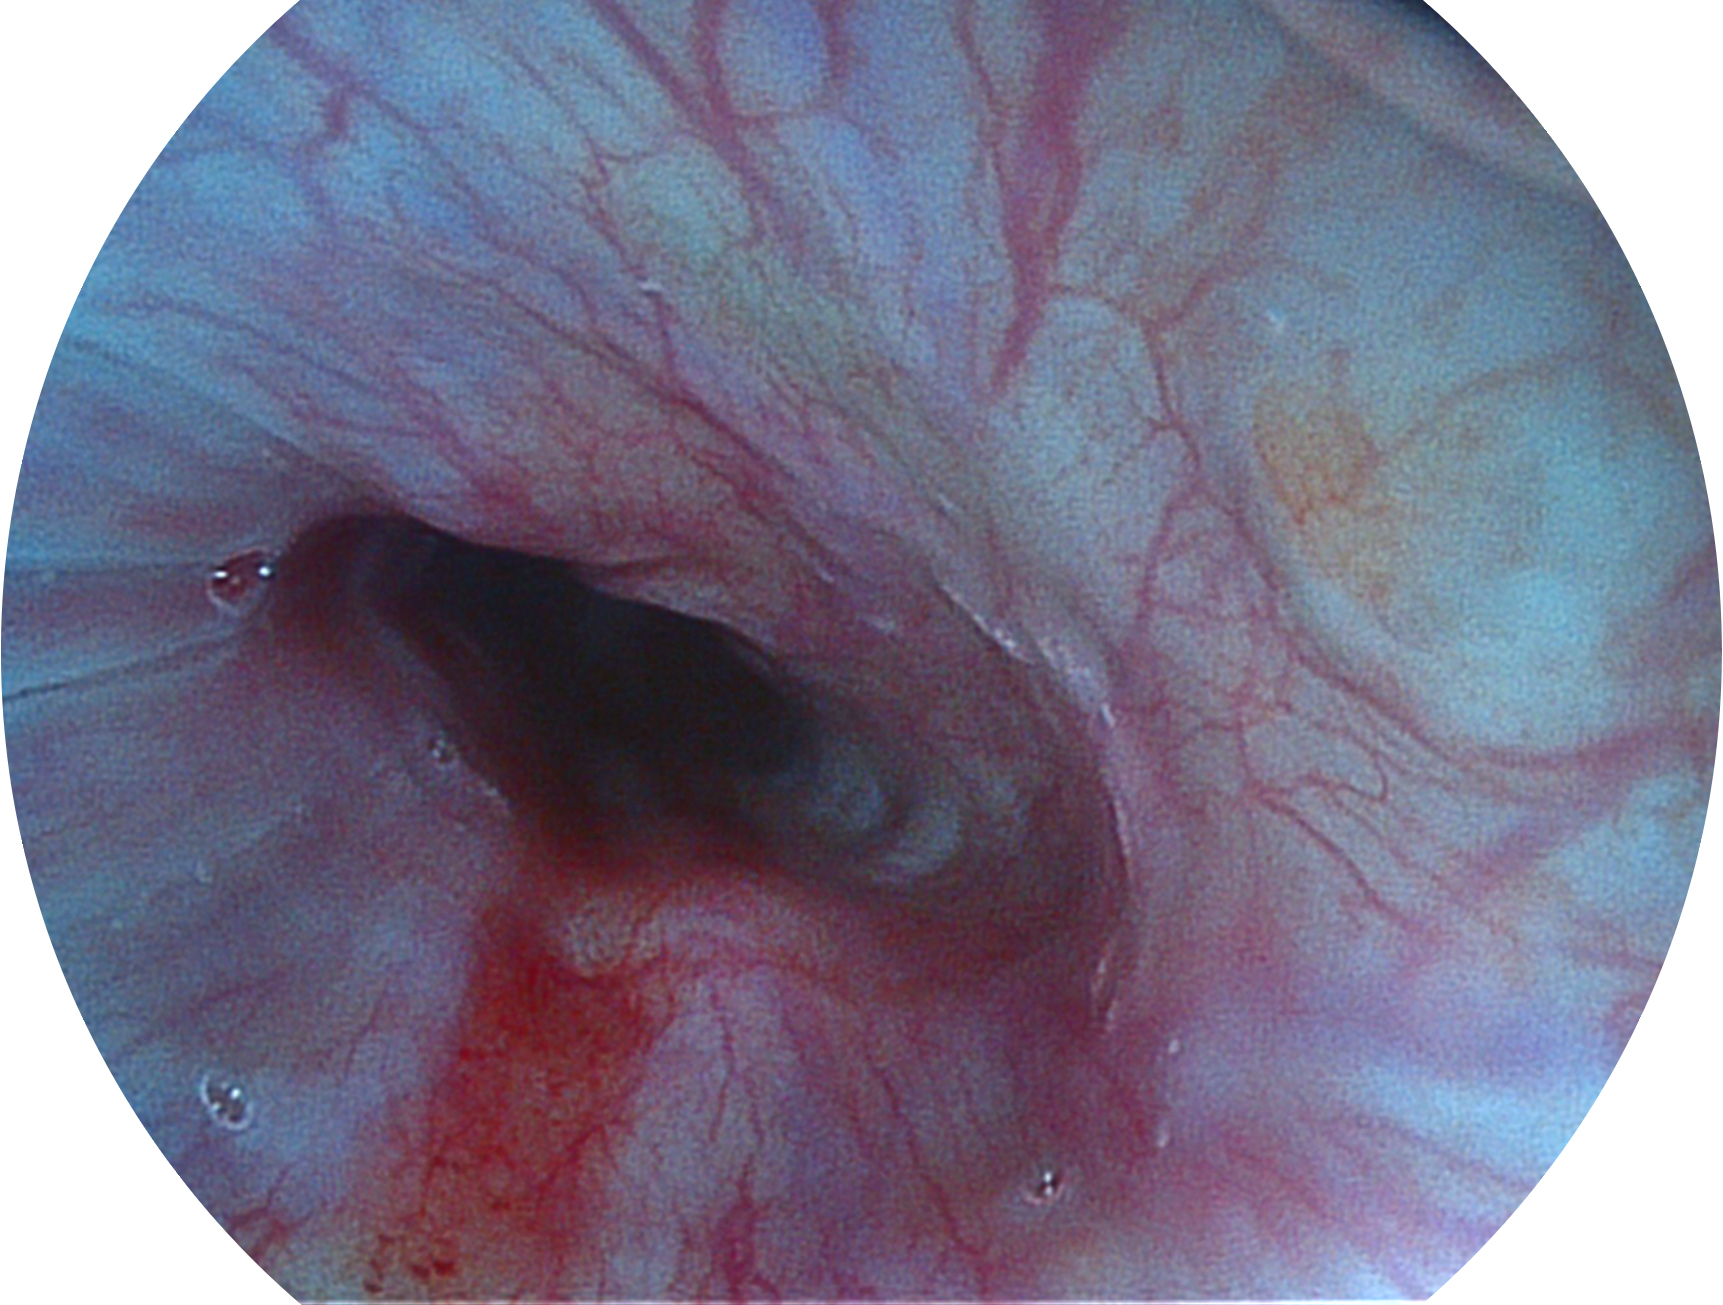

db真人体育官网新开发的内镜染色技术,主要是基于多波长LED 光源的开发,VLS-55Q 四波长LED 光源是由四个不同颜色的LED光按照相应照明模式所规定的特定发光比例进行合束后形成,合束后形成的照明光的光谱由红光、绿光、蓝光及蓝紫光这四个不同的波段范围构成。具有更高光谱自由度,通过光谱比例的控制,实现了聚谱成像技术,英文全称为“Spectral Focused Imaging, SFI”,缩写为“SFI”和光电复合染色成像技术,英文全称为“Versatile Intelligent Staining Technology, VIST”,缩写为“VIST”。